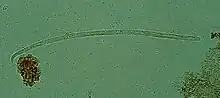

| Onchocerca volvulus, the causative agent of river blindness | |

Onchocerca volvulus is a filarial (arthropod-borne) nematode (roundworm) that causes onchocerciasis (river blindness), and is the second-leading cause of blindness due to infection worldwide after trachoma. It is one of the 20 neglected tropical diseases listed by the World Health Organization, with elimination from certain countries expected by 2025.[2]

O. volvulus parasites obtain nutrients from the human host by ingesting blood or by diffusion through their cuticle. They may be able to trigger blood-vessel formation because dense vascular networks are often found surrounding the worms.[6] They are distinguished from other human-infecting filarial nematodes by the presence of deep transverse striations.[7]

It is a dioecious species, containing distinct males and females, which form nodules under the skin in humans. Mature female worms permanently reside in these fibrous nodules, while male worms are free to move around the subcutaneous tissue. The males are smaller than females, with male worms measuring 23 mm in length compared to 230–700 mm in females.[7]

The release of oocytes (eggs) in female worms does not depend upon the presence of a male worm, although they may attract male worms using unidentified pheromones.[8] The first larval stage, microfilariae, are 300 μm in length and unsheathed, meaning that when they mature into microfilariae, they exit from the envelope of the egg.[9]